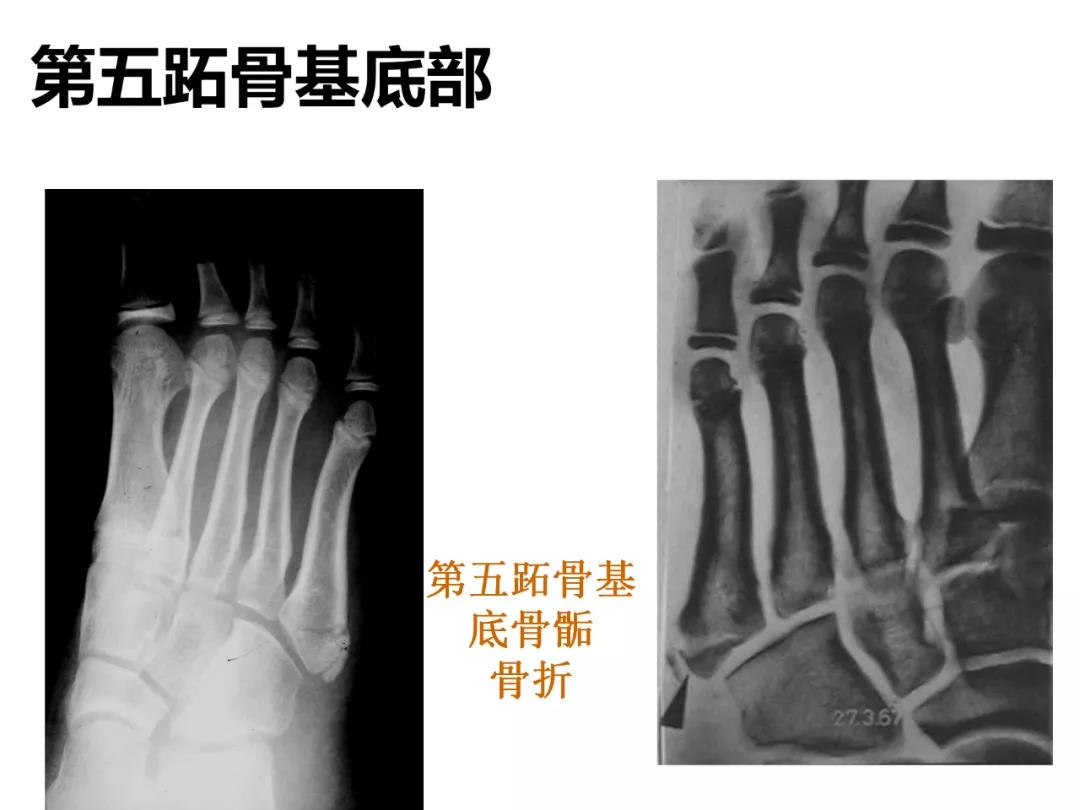

小儿骨科X线片汇总,临床读片宝典!